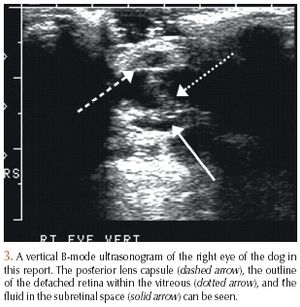

A 12-year-old 57-lb (26-kg) castrated male Siberian husky was presented to the Colorado State University Veterinary Teaching Hospital for evaluation of blindness of three weeks' duration, depression, and polydipsia.